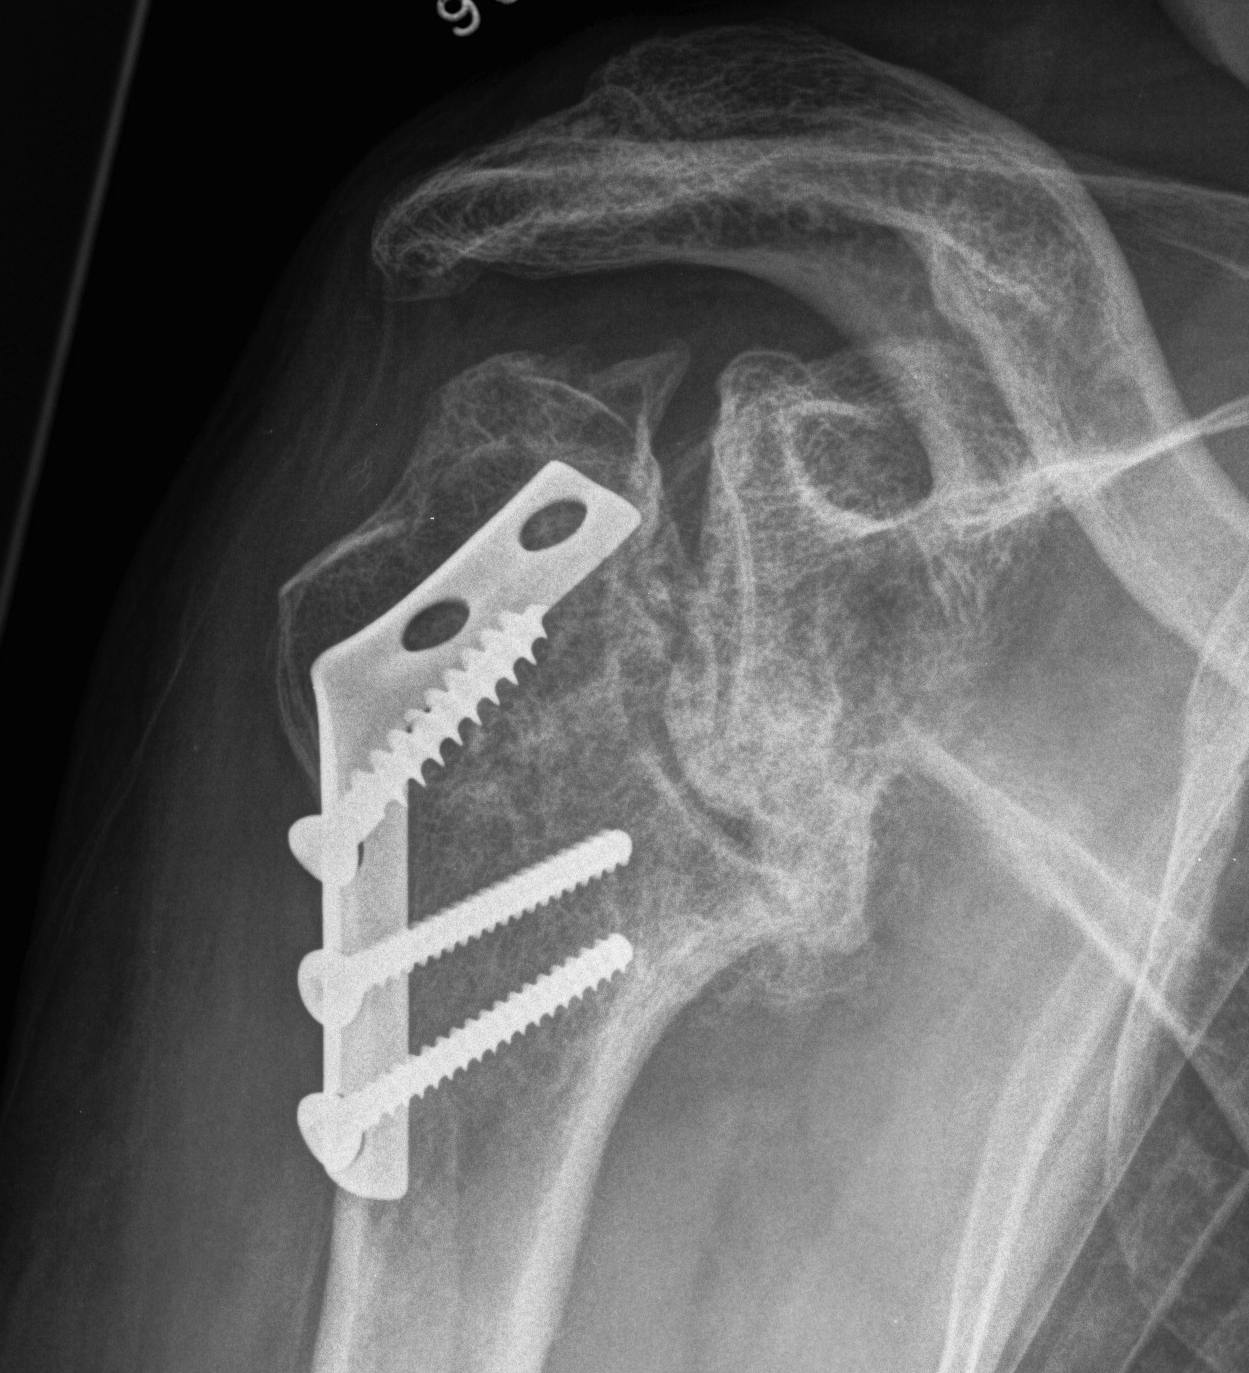

proximal humerus fracture Background ORIF with locking plate Arthroplasty Greater tuberosity fractures Lesser tuberosity fractures / avulsions Book traversal links for Proximal humerus fractures ‹ Pectoralis Major Tears Up Background ›